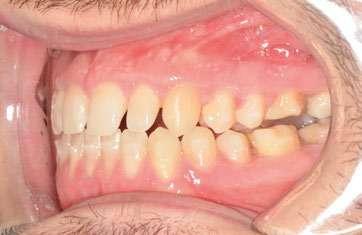

2. Análisis intraoral (Ilustración 2 y 3):

 Clase III molar y canina de Angle bilateral.

 Mordida abierta anterior > 3 mm.

 Compresión maxilar junto con mordida cruzada posterior bilateral.

 Línea media inferior desviada 2 mm hacia la derecha.

Ilustración 2. Fotografías intraorales iniciales de estudio.

Fase 2: corrección con alineadores Una vez corregida la discrepancia transversal y finalizado el periodo de control, el tratamiento continuó con alineadores Spark™, con un protocolo de uso de 22 horas diarias y cambios de alineadores cada 10 días. El tratamiento con alineadores se planificó en 2 etapas. Una primera etapa para abordar el plano vertical y una etapa final para abordar el plano sagital.

Corrección sagital (Ilustración 9):

 Corrección de la inclinación corono-distal de los premolares en el cuarto cuadrante mediante elásticos intermaxilares.

Ilustración 9. Fotografías intraorales tras el 2º set de alineadores Spark™ (corrección sagital).